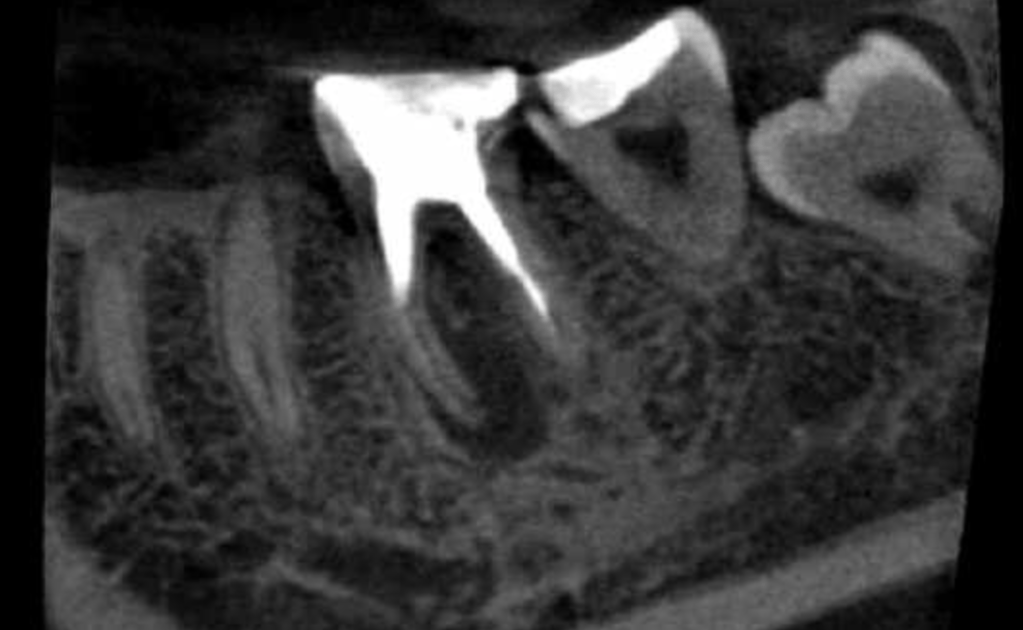

Vertical root fracture